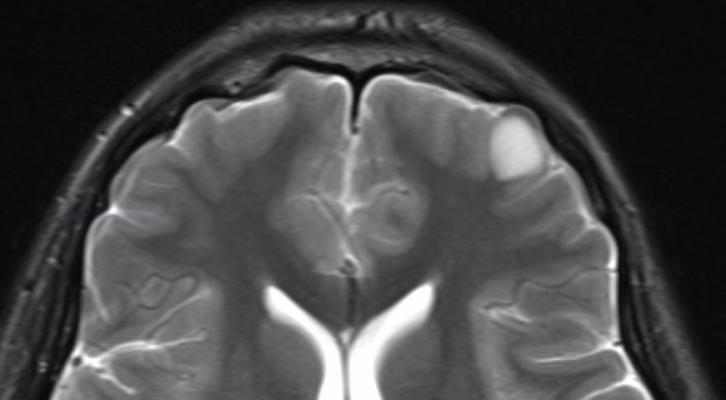

Show brain tumor at right parietal lobe of cerebrum. A ct scan or an mri report usually detects a benign brain tumor without difficulty. This program is designed to originally work with tumor detection in brain mri scans, but it can also be used for cancer diagnostics in other organ scans as well. There are different brain tumor detection and segmentation methods to detect and segment a brain tumor from mri images.